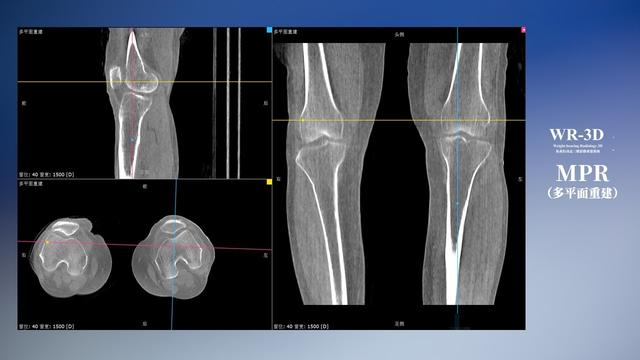

普通平片扫描与WR-3D扫描前后诊断结果对比

在负重位状态下,数字化X线三维扫描与重建,能够更好的呈现受检者关节受力改变的状态。广东会科技创新的WR-3D动态三维影像重建系统,通过数字化X线摄影完成三维扫描并重建三维影像信息,包括断层图像重建、MPR多平面重建、MIP重建以及VR体绘制。其扫描时间短,剂量相较于CT设备大幅缩减,同时成本更低,在临床诊断以及医疗方案制定中具有极大的价值意义。而相较于普通平片下的负重位扫描,负重位动态三维影像重建技术能够避免二维状态下的组织结构重叠、密度分辨率不足、组织解剖结构难以分辨等问题。WR-3D支持多角度的三维观察,能全面的呈现被检查部位在多个角度下的三维影像信息,极大的降低了二维负重位检查带来的漏诊率。

广东会科技WR-3D负重位动态三维影像重建图像